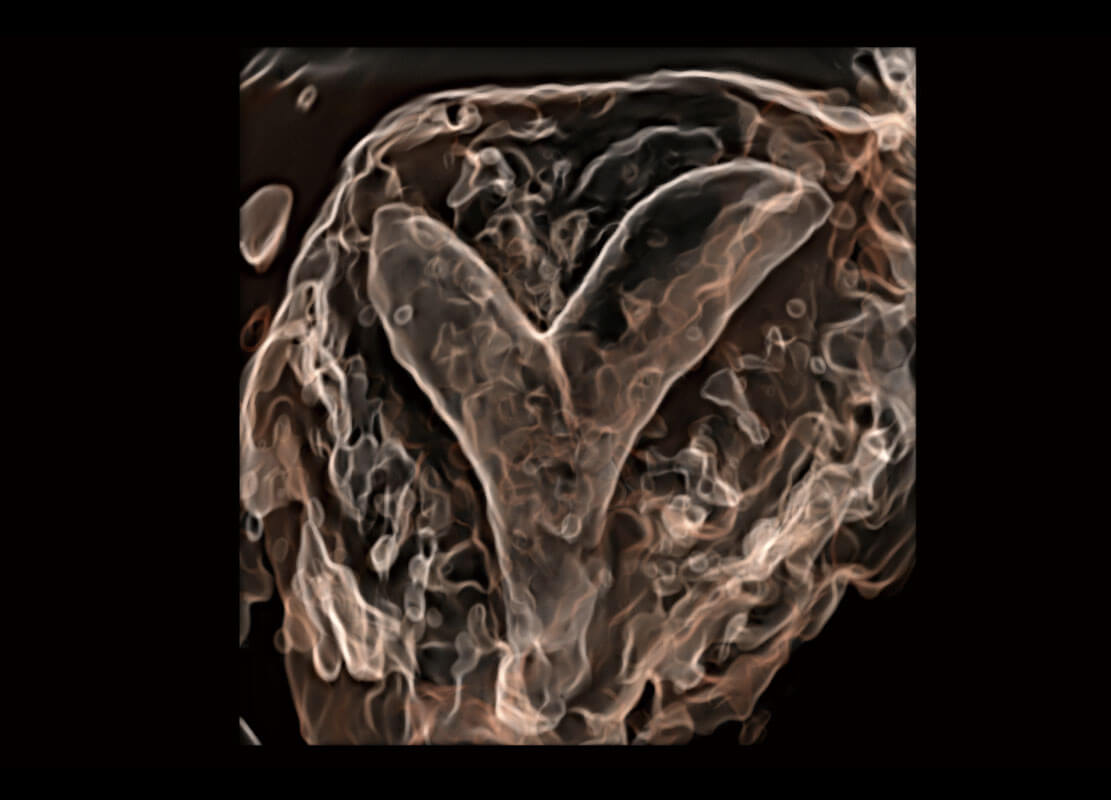

腔内三维-光影成像

右室双出口